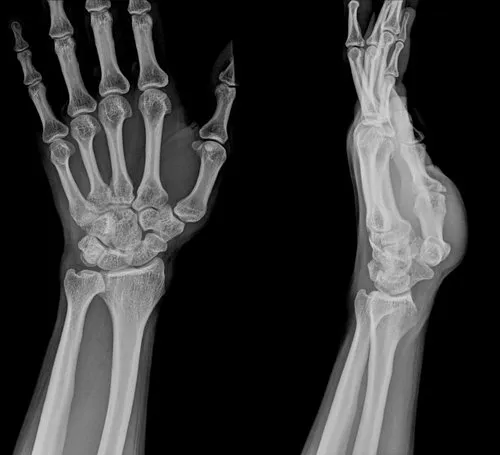

Rehabilitacja po złamaniu nadgarstka to kluczowy etap w procesie powrotu do pełnej sprawności. Czas jej trwania może się znacznie różnić w zależności od wielu czynników, takich jak rodzaj urazu, sposób leczenia, wiek pacjenta oraz zaangażowanie w proces rehabilitacji. Zazwyczaj rehabilitacja trwa od kilku tygodni do kilku miesięcy, a w niektórych przypadkach może nawet sięgać roku lub dłużej.

Czas trwania rehabilitacji po złamaniu nadgarstka może być różny w zależności od wielu czynników. Ogólnie rzecz biorąc, rehabilitacja trwa od kilku tygodni do kilku miesięcy, a w bardziej skomplikowanych przypadkach może sięgać nawet roku. Proces rehabilitacji można podzielić na kilka kluczowych etapów, które obejmują gojenie kości, unieruchomienie oraz aktywną rehabilitację.

Pierwszy etap, czyli gojenie kości, zazwyczaj trwa od 6 do 8 tygodni. W tym czasie kość regeneruje się, a pacjent może być zobowiązany do noszenia gipsu lub innego rodzaju unieruchomienia. Po tym okresie następuje czas, w którym gips jest zdejmowany, a pacjent przechodzi do aktywnej rehabilitacji, która może trwać od 4 do 16 tygodni, w zależności od rodzaju złamania.

Etap gojenia kości jest kluczowy dla dalszego procesu rehabilitacji. W tym czasie organizm odbudowuje uszkodzone tkanki, co jest niezbędne do przywrócenia pełnej funkcjonalności nadgarstka. W przypadku złamań z przemieszczeniem, czas gojenia może być dłuższy, co wymaga dodatkowego monitorowania przez specjalistów.